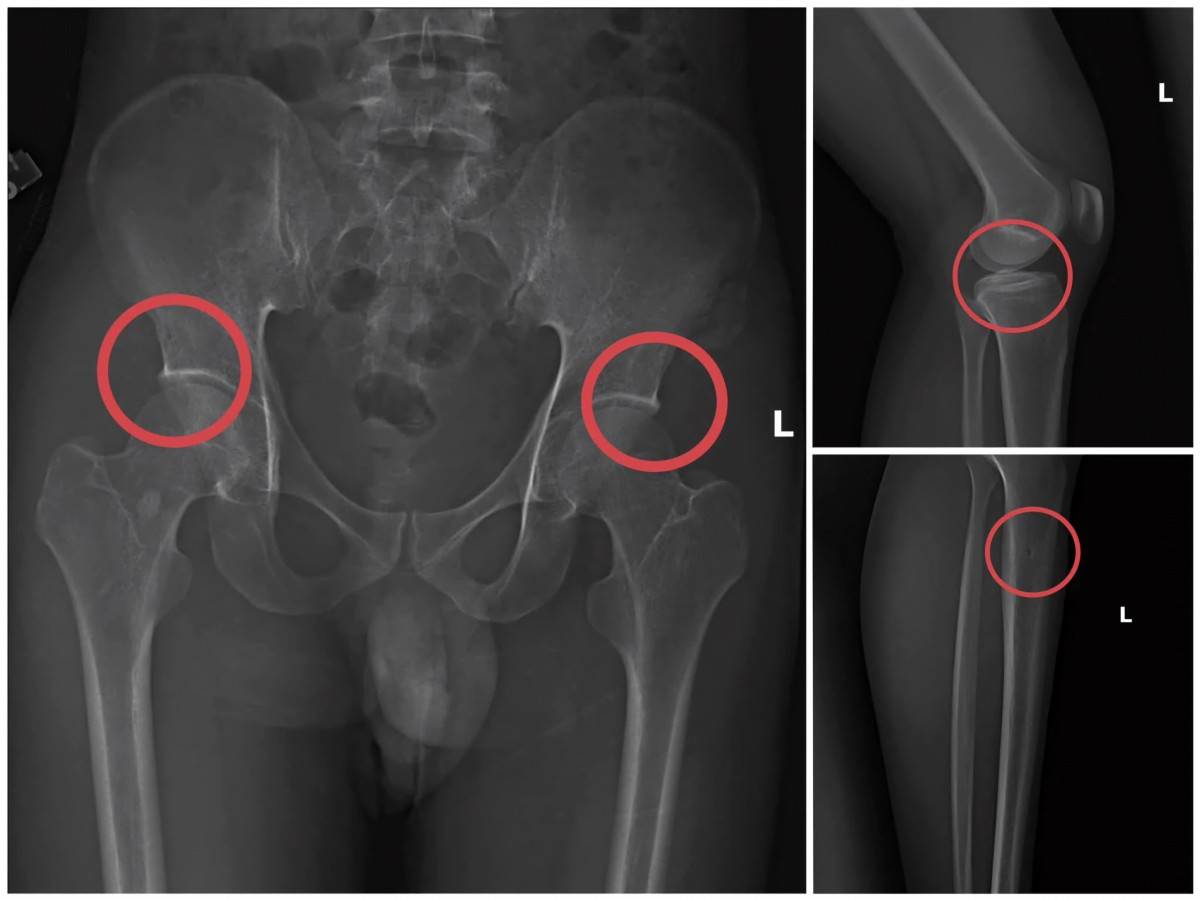

Bản phim chụp X-quang tổn thương xương do các đối tượng tự tạo ra.

Theo điều tra, Châu trực tiếp tiêm thuốc mê rồi dùng kim tiêm, búa, đinh và các vật cứng tác động vào cơ thể người tham gia để tạo vết nứt, vỡ xương tương tự tai nạn thật. Sau khi gây thương tích, Châu hướng dẫn dựng hiện trường giả như điện giật, ngã suối… để hợp thức hóa bệnh án và hoàn thiện hồ sơ yêu cầu chi trả.

Thủ đoạn được tính toán kỹ lưỡng nhằm tạo thương tích đúng vị trí có mức chi trả cao, gây khó khăn cho doanh nghiệp bảo hiểm trong việc phát hiện gian lận.